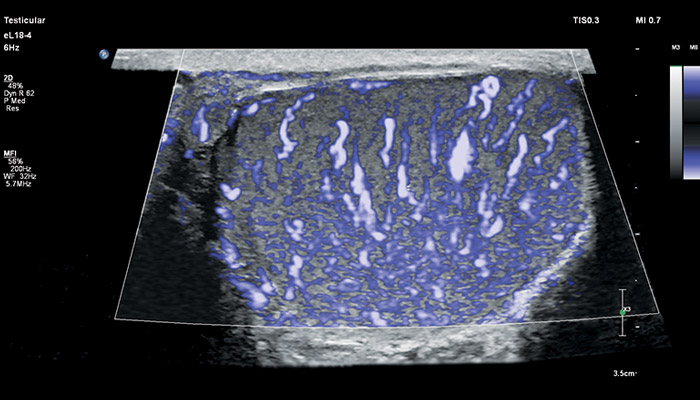

Линейный матричный датчик eL18-4 поддерживает режим высокочувствительной визуализации кровотока (Philips MicroFlow Imaging), новый запатентованный метод, который обеспечивает инновационный подход к оценке сосудистого русла. Визуализация MicroFlow преодолевает многие барьеры, связанные с традиционными методами обнаружения кровотока в малых сосудах, обеспечивая высокое разрешение при минимальных артефактах.

Метод MicroFlow Imaging поддерживает высокую частоту кадров и качество изображения, применяет инновационные методы сокращения артефактов. Варианты вычитания 2D-изображений, смешивания и параллельного отображения обеспечивают превосходную визуализацию в различных клинических случаях.